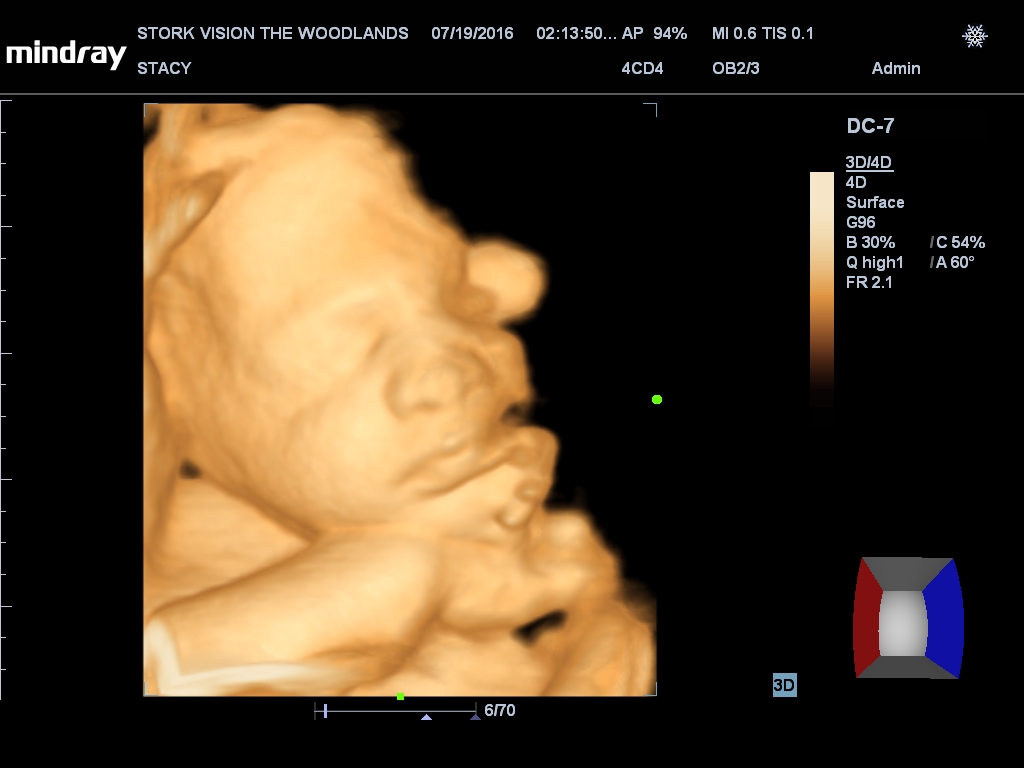

Best moment the week: Seeing Juliette on the 3D/4D ultrasound. So amazing!

Gender: GIRL!